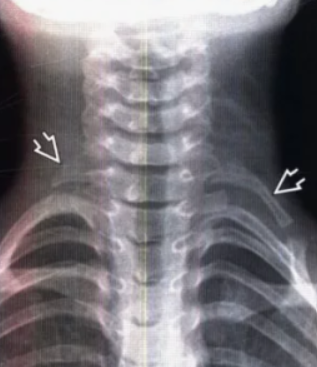

Второй по частоте причиной компрессии СНП в области плечевого пояса являлось шейное ребро. Являясь врождённой, у большинства людей эта патология может в течение всей жизни не проявляться. Как было отмечено выше, данный синдром был представлен 2 формами - ДШР и РШР. Когда длина шейного ребра составляла более 25 мм, то это обозначалось как ДШР, если менее - РШР. Шейные рёбра отходили от поперечного отростка VII шейного позвонка (CVII) и формировали с ним сустав. Свободный конец шейного ребра направлялся в сторону первого ребра, формируя с ним дополнительный сустав. Нередко оно срасталось с первым ребром без образования сустава. Основным методом диагностики этой формы являются рентгенография и КТ. На рис. 2 отражены рентгенологические признаки двухстороннего процесса (ДШР+РШР).